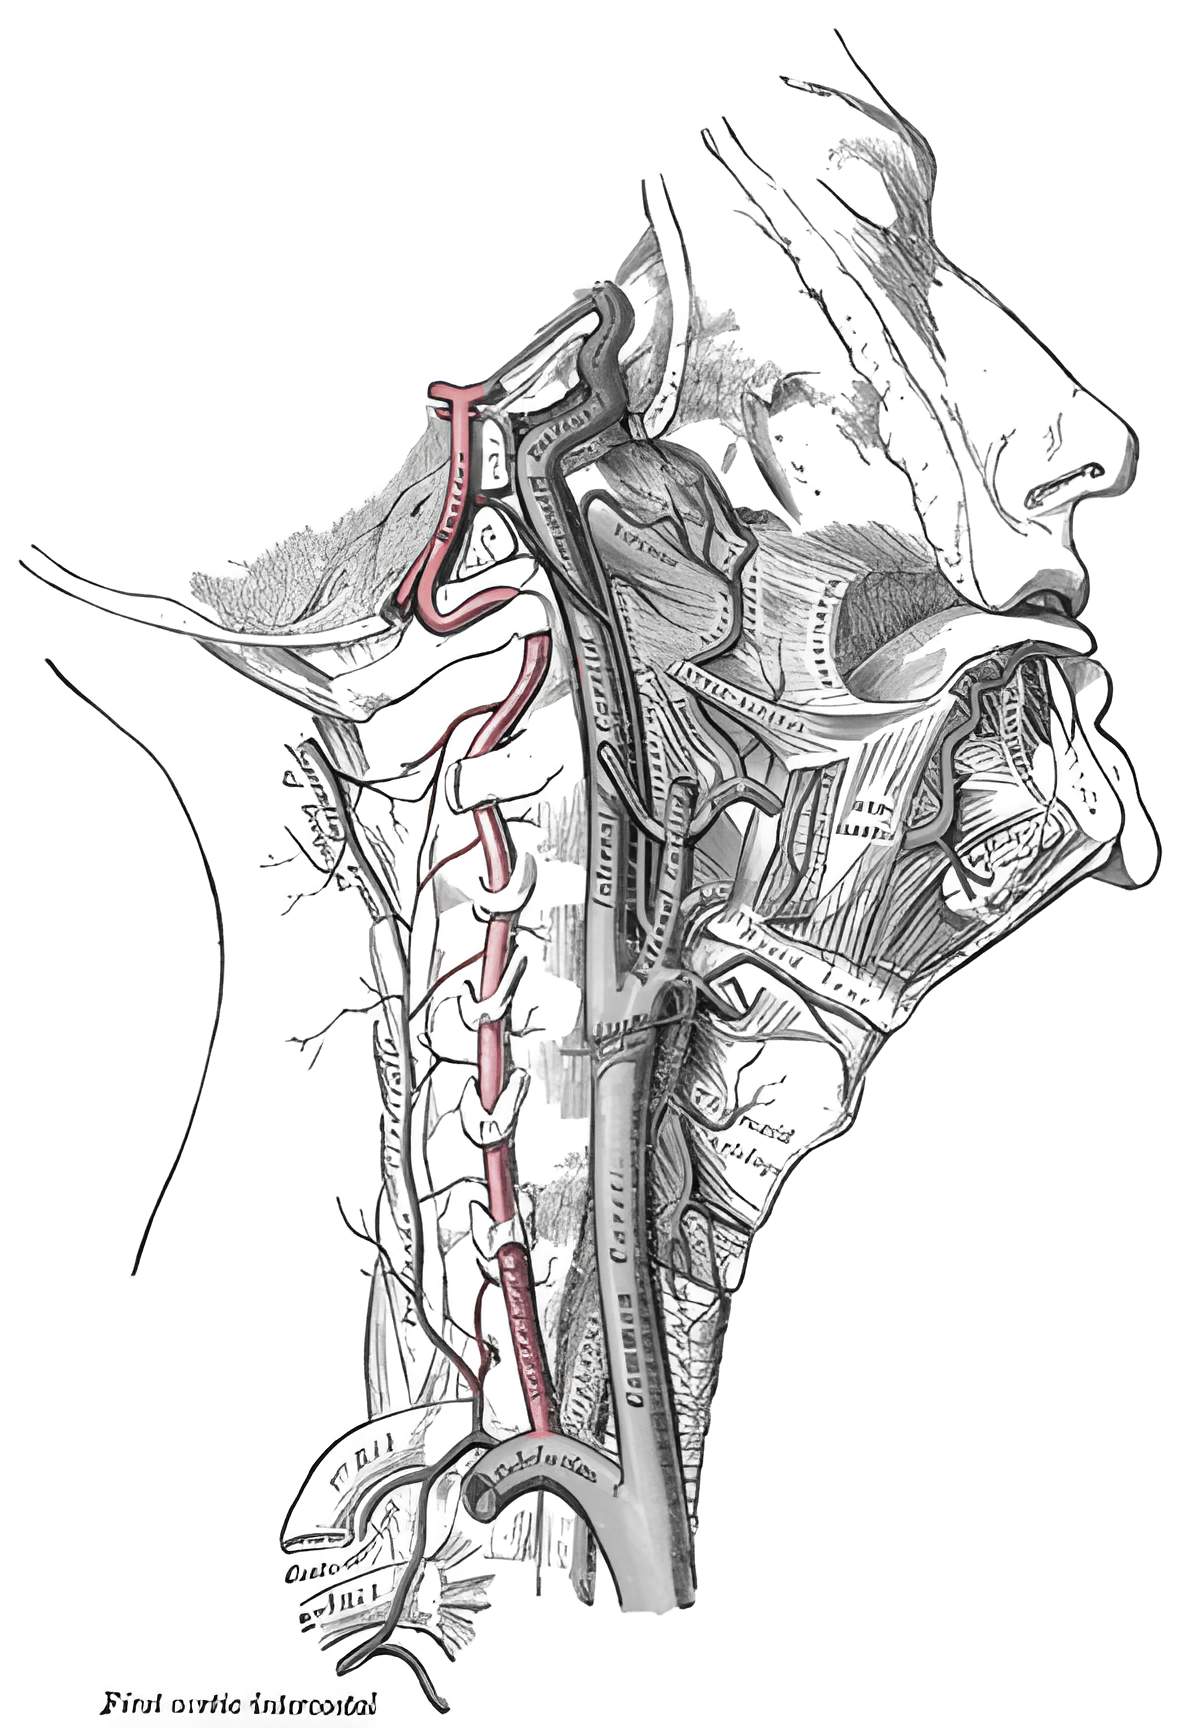

Die paarig angelegte Arteria verterbralis entspringt aus der Arteria subclavia und vereinigt sich zur Arteria basilaris. Die Arteria vertebralis kann in vier Segmente unterteilt werden[^1]:

Segmente

Segment | Beschreibung | Arterienabgänge [^2] |

Prevertebrales Segment (V1) | Das V1 Segment verläuft vom Arterienabgang bis zum Eintritt in das Foramen transversarium, üblicherweise auf Höhe HWK6 | Keine |

Foraminales Segment (V2) | Das V2 Segment verläuft vertikal in den Foramina transversaria in der Halswirbelsäule entlang. |

|

Predurales Segment (V3) | Das V3 Segment verläuft vom Austritt der Arteria vertebralis aus dem Foramen transversarium des Axis bis zum Eintritt der Arteria vertebralis in die Dura mater. |

Intradurales Segment (V4) | Das V4 Segment verläuft vom sehr variabel gelegenen Duradurchtritt bis zur Vereinigung zur Arteria basilaris. |

Abbildung